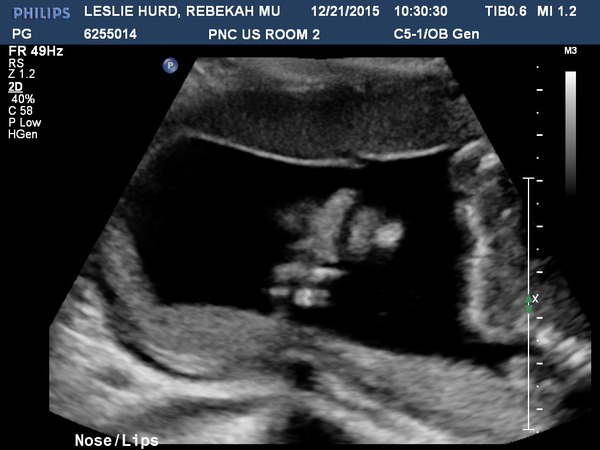

21 Week Ultrasound

10:00:00       Monday 21 December 2015